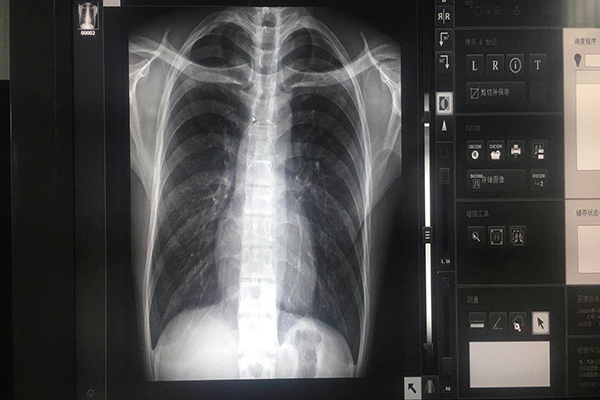

顯示器的亮度是會(huì)隨著時(shí)間而衰減的,普通顯示器由于沒(méi)有穩(wěn)定的亮度控制和校準(zhǔn),不但衰減較快,平時(shí)使用時(shí),也由于受環(huán)境的影響,其亮度不能長(zhǎng)時(shí)間的維持在一個(gè)對(duì)人體肉眼合適的水平上,而醫(yī)學(xué)灰階顯示器考慮到這一個(gè)問(wèn)題,采取了穩(wěn)定的亮度控制技術(shù),對(duì)顯示亮度所反饋的信息隨時(shí)進(jìn)行校準(zhǔn),使其始終保持在標(biāo)準(zhǔn)亮度之上,符合臨床的閱片標(biāo)準(zhǔn)。

亮度就是灰階顯示器上顯示圖像有多么明亮,顯示越明亮圖像中的能夠產(chǎn)生的動(dòng)態(tài)范圍就越大,使人們?cè)趫D像中分辨更多的色調(diào),這種動(dòng)態(tài)范圍必須提供全8bit灰階圖像(即256不同色調(diào))。